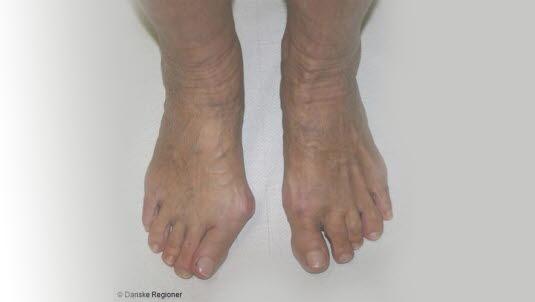

Hallux valgus, skjev stortå

Hallux valgus er en feilstilling av stortåen slik at den dreier i retning lilletåen. Samtidig er stortåens grunnledd forskjøvet innover i retning den andre foten.

Hallux valgus er en skjevstilling av stortåen som er vinklet i retning lilletåen, og der benet innenfor stortåen vinkles motsatt og innover mot den andre foten. Tilstanden er ofte ledsaget av ubehag og smerter fra stortåens grunnledd. Leddet hovner opp og blir svært markert og prominerende på innsiden av foten. Forandringene i foten kan gjøre det vanskelig å finne sko som passer godt.

Hallux valgus er en svært vanlig tilstand som er langt hyppigere hos kvinner enn hos menn. Forekomsten varierer mellom studier, men øker med alderen og oppgis i noen studier til nær 20 prosent blant voksne kvinner.